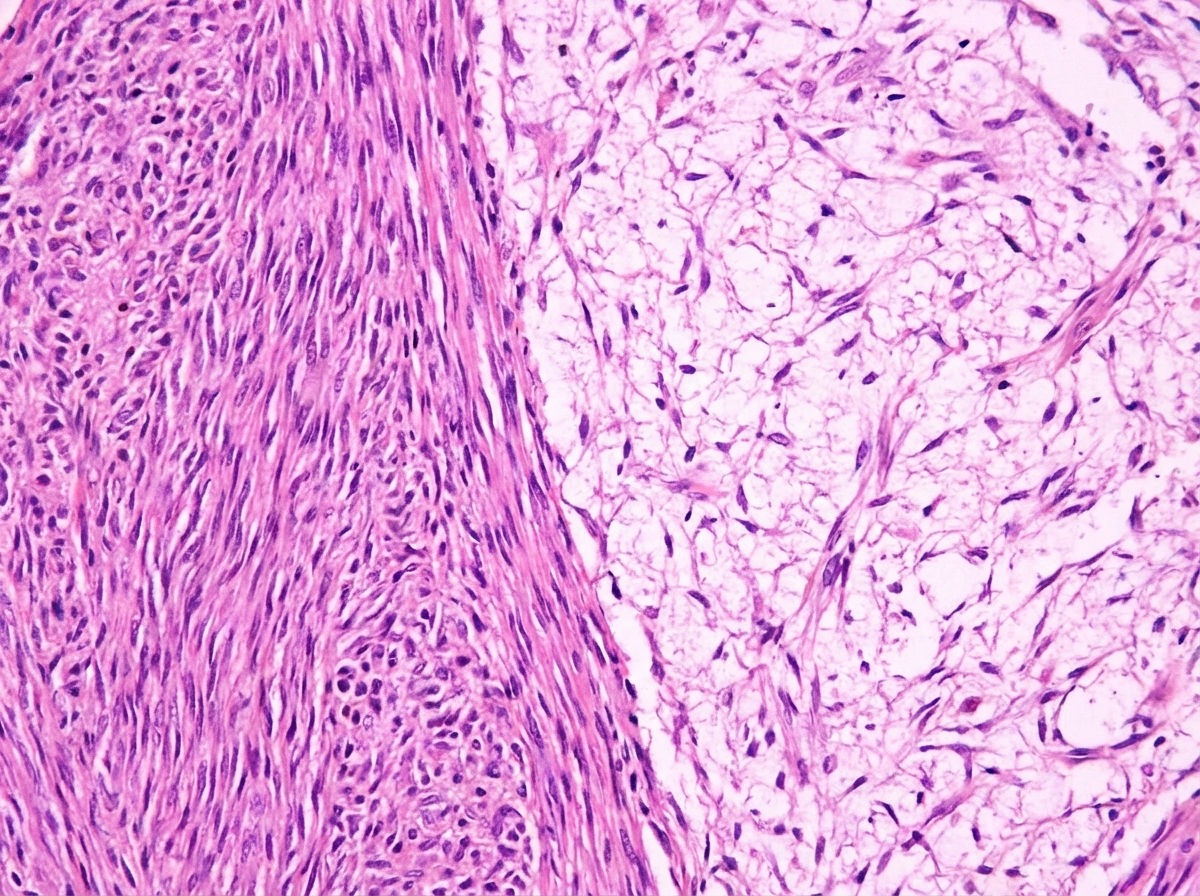

A 35-year-old man, with a history of neurofibromatosis type 2 (NF2) diagnosed 2 years ago, presents with hearing loss in the right ear and tinnitus. Patient says that symptoms have been gradually progressive. He has difficulty hearing speech as well as loud sounds. He also gives a history of occasional headaches and vertigo on and off for 1 month, which is unresponsive to paracetamol. His vitals include: blood pressure 110/78 mm Hg, temperature 36.5°C (97.8°F), pulse 78/min and respiratory rate 11/min. Tuning fork tests reveal the following: Left Right Rinne’s test Air conduction > bone conduction Air conduction > bone conduction Weber test Lateralized to left ear Other physical examination findings are within normal limits. An MRI of the head is ordered which is as shown in image 1. A biopsy is done which shows cells staining positive for S100 but negative for glial fibrillary acidic protein (GFAP). The histopathological slide is shown in image 2. What is the most likely diagnosis?